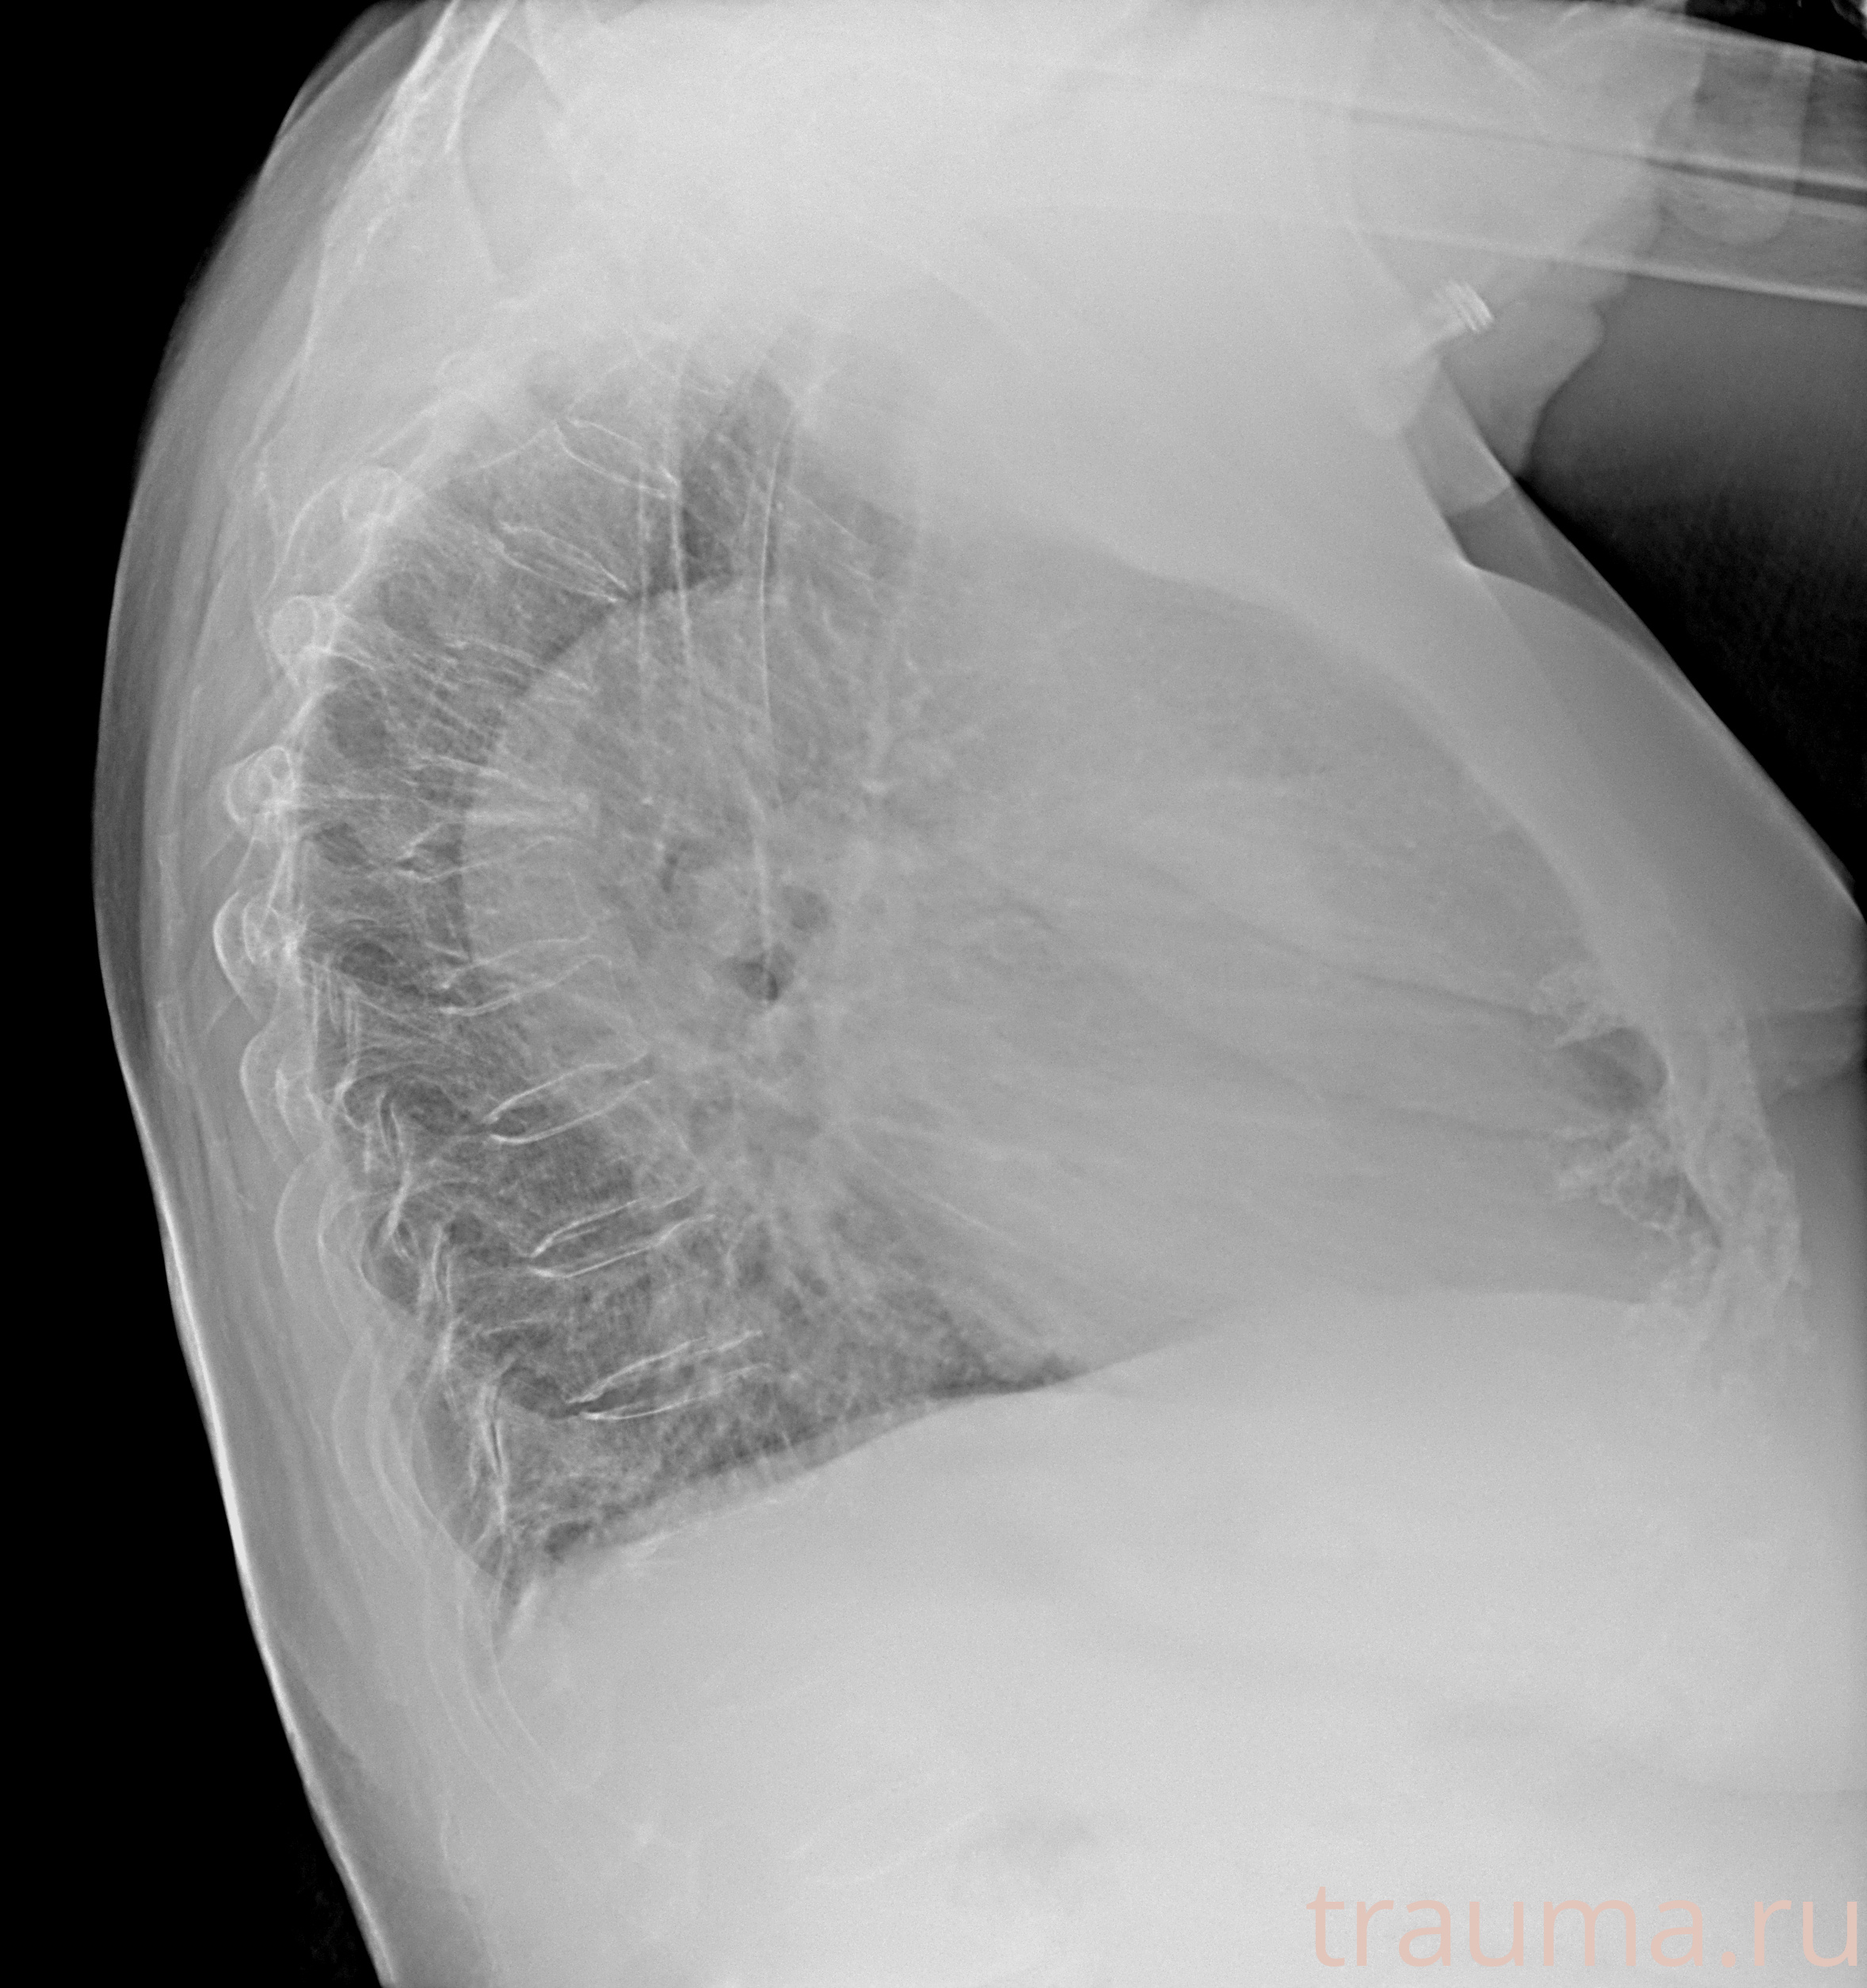

Рентген на дому: по вашему адресу приезжает врач-рентгенолог, травматолог-ортопед с мобильным рентгеновским аппаратом, проводит диагностику травмы или заболевания, делает необходимые рентгенограммы, дает рекомендации по дальнейшему лечению. Получить качественные снимки в домашних условиях возможно благодаря уникальной методике, разработанной МосРентген Центром для института  Склифосовского

при переломе шейки бедра и пневмонии от компании МосРентген Центр - партнера Института имени Склифосовского